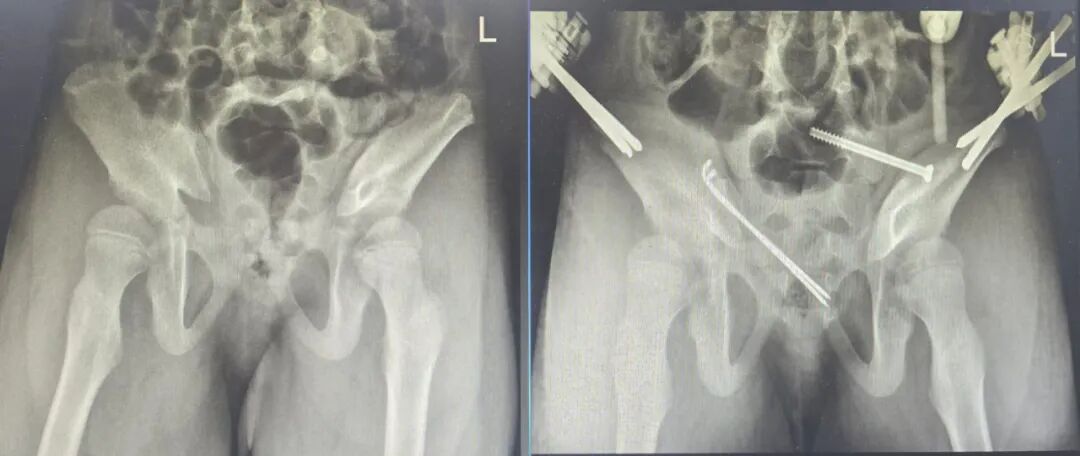

骨盆C型骨折是创伤骨科中极为复杂的骨折类型,骨折移位明显、稳定性极差,治疗难度极大。骨科三病区接诊的一位50多岁患者,遭遇严重外伤导致骨盆C型骨折,若采用传统单一固定方式,难以实现骨折端的稳定复位。团队勇于突破技术瓶颈,创新性采用骨盆骨折闭合复位骶髂螺钉固定 +前环InFix固定技术,通过微创方式同时实现骨盆后环与前环的稳定固定,既保证了骨折复位的精准性,又最大程度保留了骨盆的生理功能。术后患者恢复顺利,各项功能指标逐步正常,该技术的成功应用,填补了安顺地区在复杂骨盆骨折联合微创固定领域的空白,标志着安顺市人民医院骨科在骨盆髋臼手术领域达到省内先进水平。

术后视频